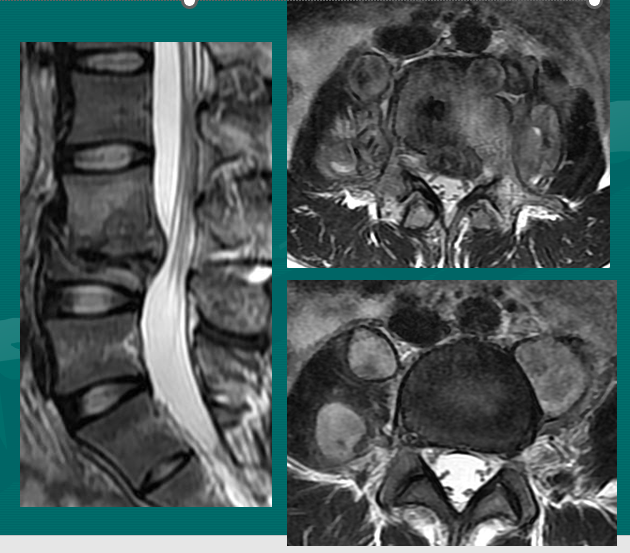

位于椎体之间的椎间盘应是白色的(含水多)。注意黑颜色(脱水的)的L5椎间盘(L5与骶骨之间的椎间盘),这代表了中度到重度的退化性椎间盘病。

后纵韧带(PLL小蓝箭头)在图像中表现为沿着每个椎体及椎间盘后缘垂直向下的黑线。有意思的是,尽管此病人有一个9mm的椎间盘突出(HNP),骨质有一定的翘起,在椎间盘平面以上可见髓核物,但后纵韧带仍然包容着突出的髓核物而没有游离出。这种情况在学术上被称作一个大的包容性椎间盘突出。

硬膜囊(红星)表现为“超白色”结构,填充在椎体后方的中央椎管内。此囊袋内有可自由浮动的由运动神经纤椎及感觉神经纤维共同组成的脊神经根(马尾)。

黄韧带(绿星)位于每个椎骨之间,增强脊柱的稳定性。此结构可变大或增厚,助长年长者易患的中央型椎管狭窄的形成。